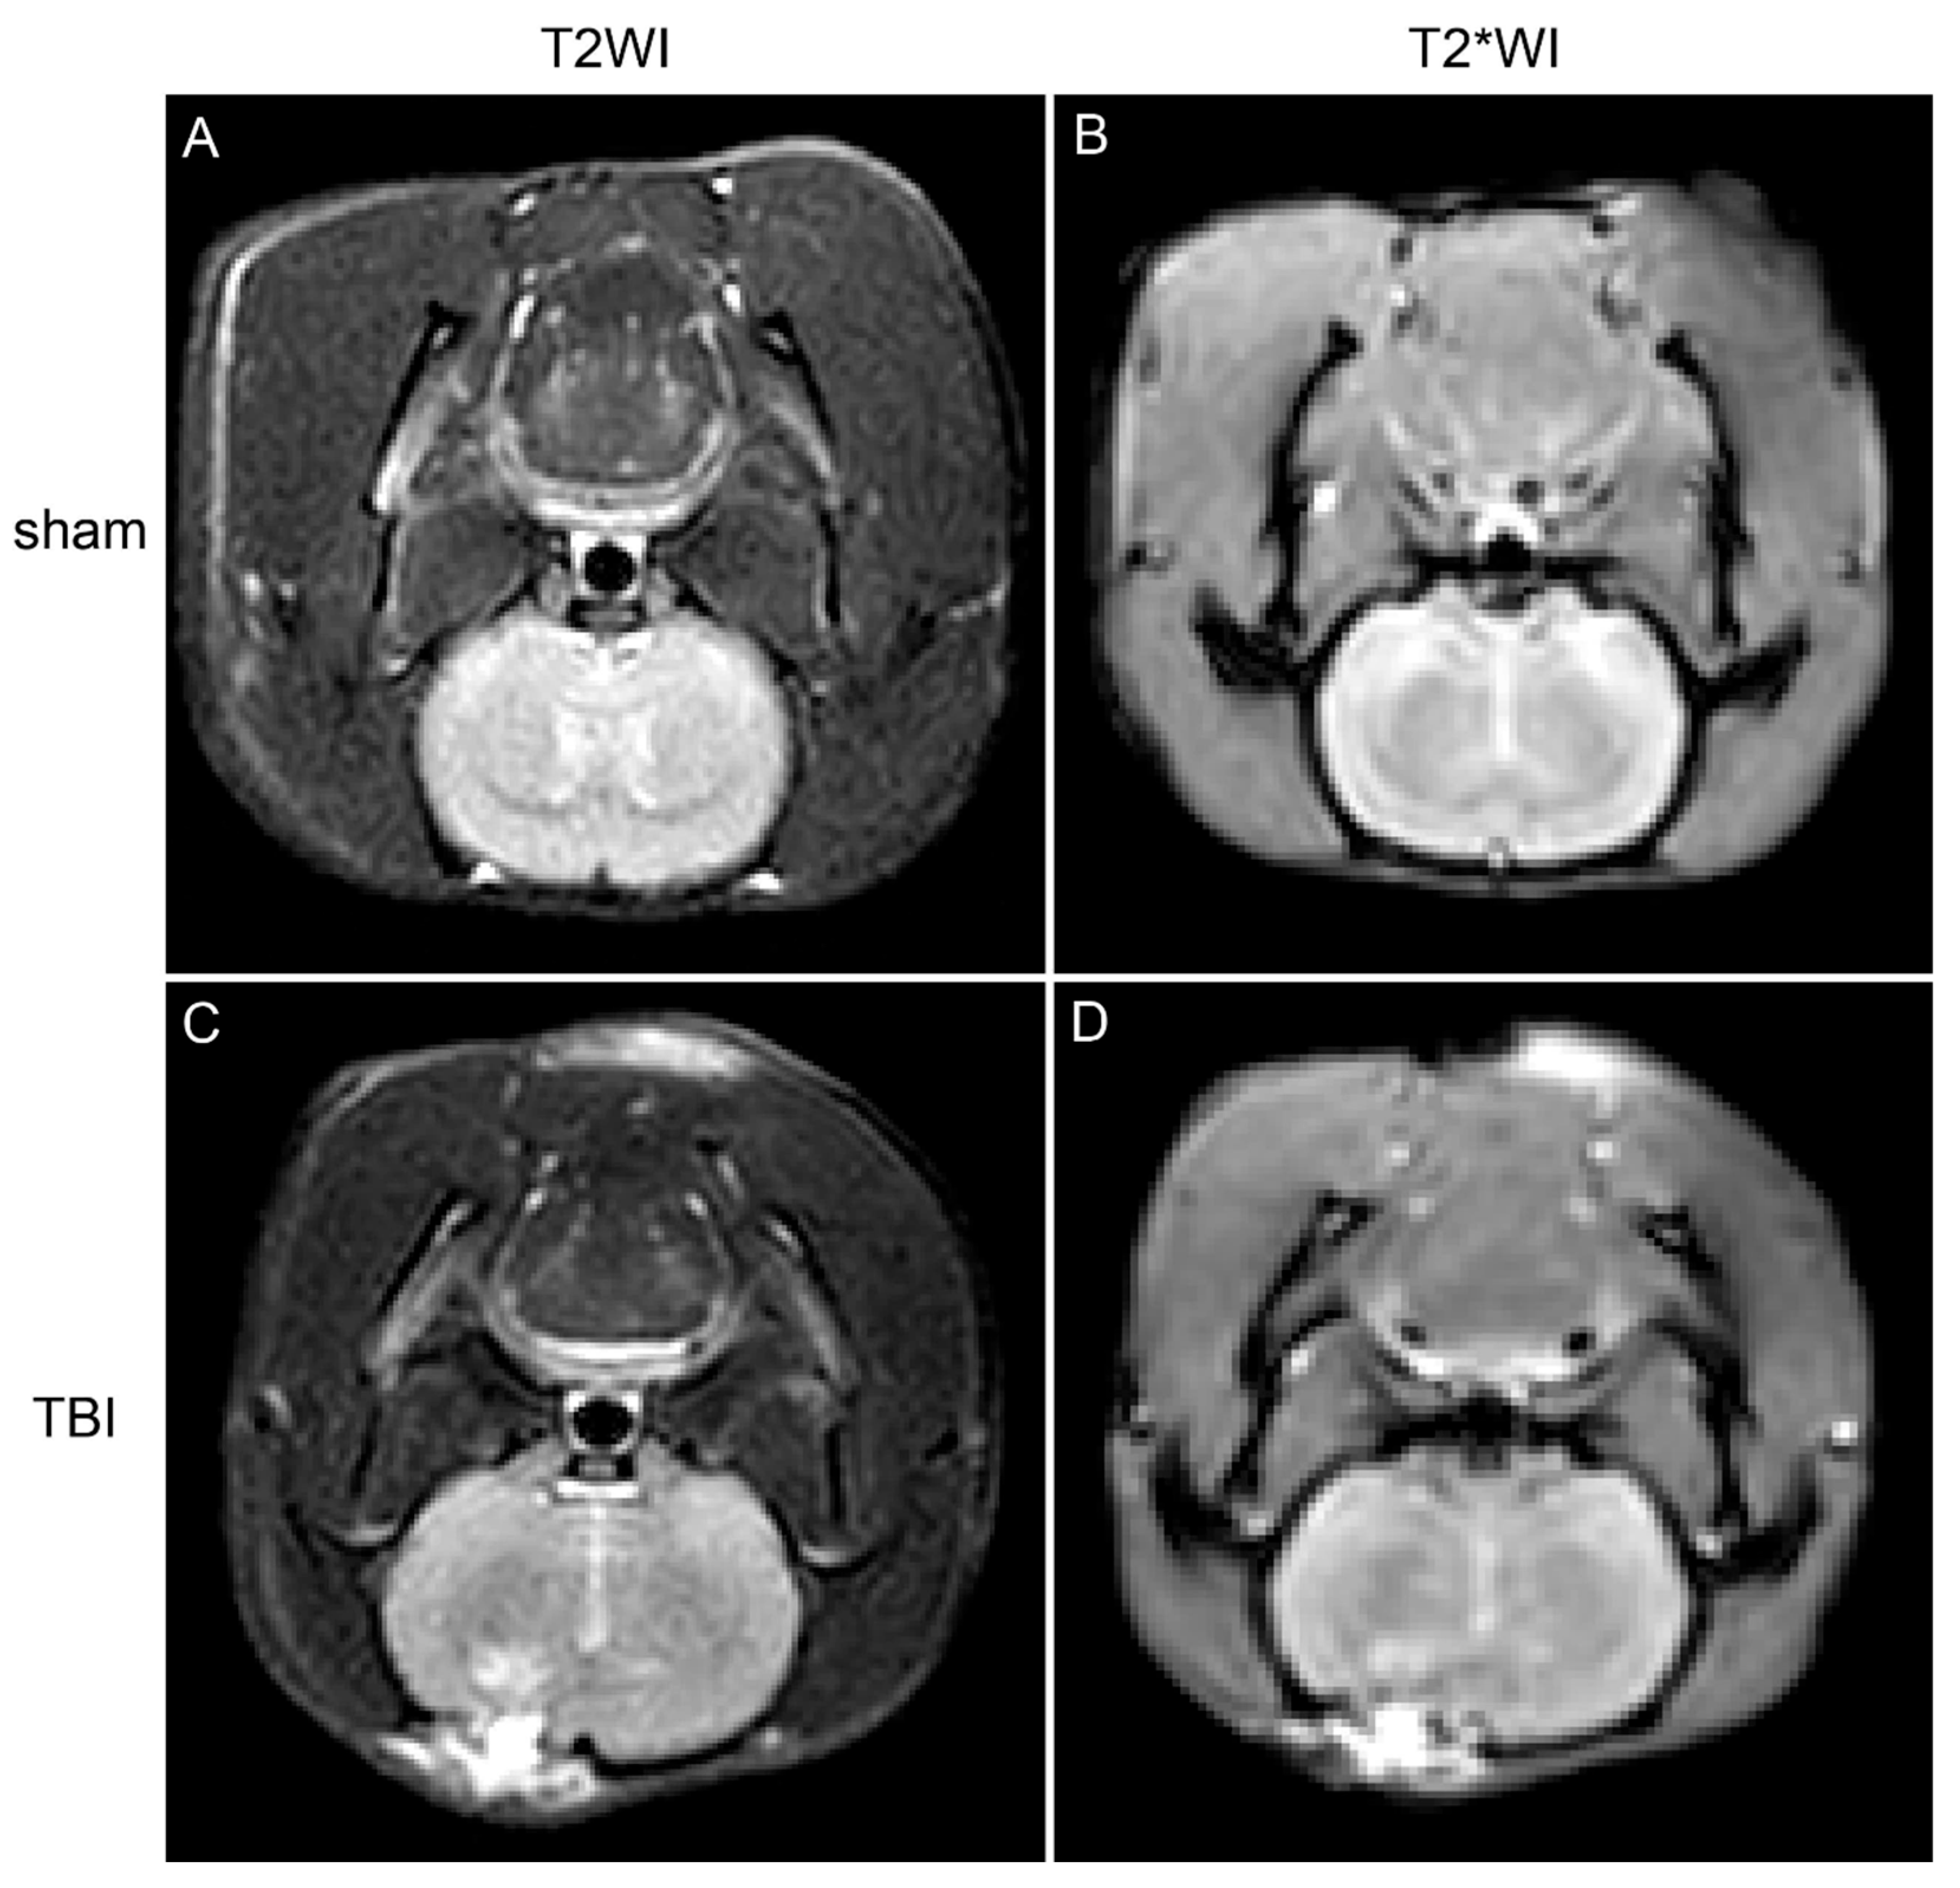

3.1. MRI Shows Iron Deposition in the Brain Tissue Surrounding the Injury Site in TBI Rats

- Coronal T2-weighted imaging (T2WI): Resolution 0.3 × 0.33 × 2 mm, Repetition Time (TR) 2000 ms, Echo Time (TE) 80 ms.

- Coronal T2* imaging (T2*WI): Resolution 0.53 × 0.53 × 2 mm, TR 510 ms, TE 16 ms, Flip Angle 18°.